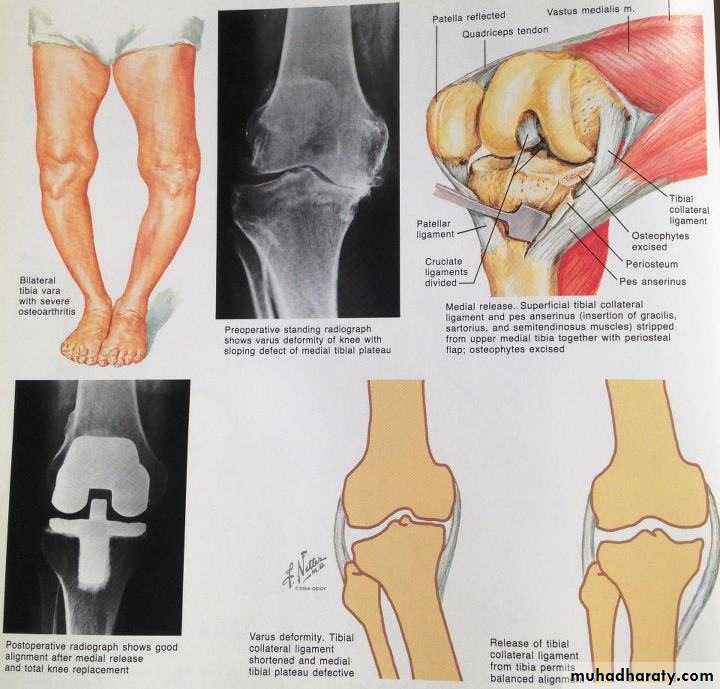

The knee is the commonest of the large joints to be affected by osteoarthritis .Often there is a predisposing factor(secondary): injury to the articular surface, a torn meniscus, ligamentous instability or preexisting deformity of the hip or knee, to mention a few. However, in many cases no obvious cause can be found (primary).RISK FACTOR

1-Cartilage breakdown usually starts in an area of excessive loading.2-changes are most marked in the medial compartment narowing of joint space.(varus)

3- sclerosis of the subchondral bone and peripheral osteophyte formation Chondrocalcinosis is common.

Age :Patients are usually over 50 years old; they tend to be overweight and may have longstanding bow-leg deformity.Pain is the leading symptom, worse after use, or on stairs. After rest, the joint feels stiff and it hurts to ‘get going’ after sitting for any length of time. Swelling is common, and giving way or locking may occur.

On examination there may be an obvious deformity (usually varus) or the scar of a previous operation. The quadriceps muscle is usually wasted.

X-ray

The anteroposterior x-ray must be obtained with the patient standing and bearing weight; only in this way can small degrees of articular cartilage thinning be revealed.1-The tibio-femoral joint space is diminished

(often only in one compartment) and there is

2-subchondral sclerosis.

3-Osteophytes and

4- subchondral cysts

2- Realignment osteotomy is often successful in relieving symptoms and staving off the need for ‘end-stage’ surgery. The ideal indication is a ‘young’ patient

(under 50 years) with a varus knee and osteoarthritis

confined to the medial compartment: a high tibial valgus

Osteotomy.

3-Replacement arthroplasty is indicated in older

patients with progressive joint destruction. This isusually a ‘resurfacing’ procedure, with a metalfemoral condylar component and a metal-backed polyethylene table on the tibial side.